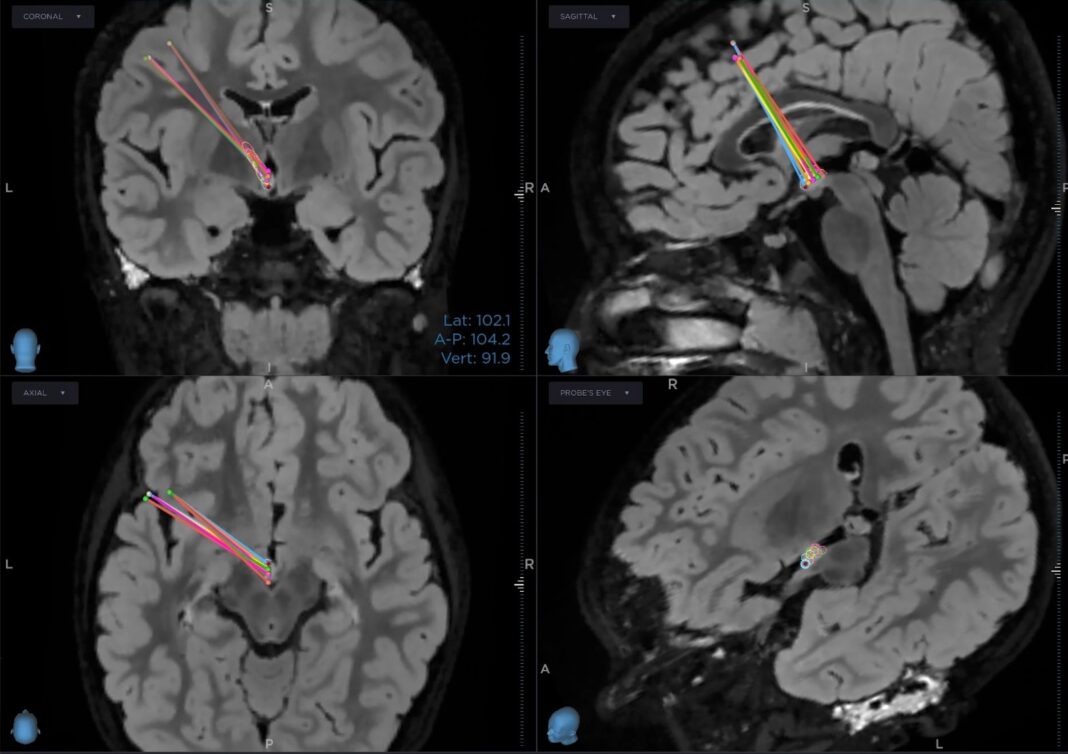

एम्स जोधपुर की विशेषज्ञ टीम ने न्यूनतम इनवेसिव स्टीरियोटैक्टिक रेडियोफ्रीक्वेंसी एब्लेशन तकनीक का उपयोग किया।

- कंप्यूटर गाइडेड स्टीरियोटैक्टिक फ्रेम तकनीक अपनाई गई

- मस्तिष्क के गहरे हिस्से में स्थित समस्या वाले ऊतक को लक्षित किया गया

- केवल लगभग 1 इंच के छोटे चीरे से सर्जरी पूरी हुई

- ओपन ब्रेन सर्जरी की जरूरत नहीं पड़ी